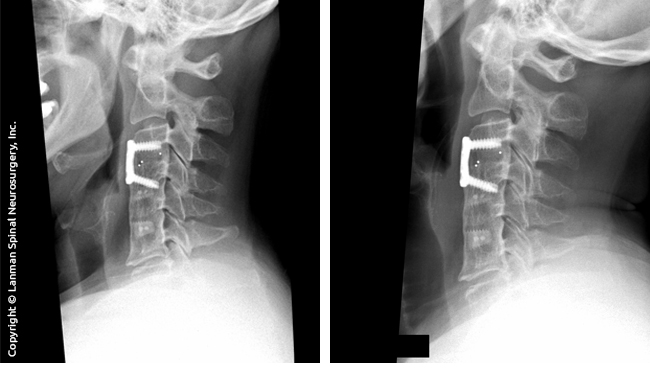

Fusion literally fuses two or more vertebral levels together as one. Major surgery is required to install rods and plates that are screwed into the bones of the affected levels. Bone grafts are added to add strength to the fusion.

The procedure requires a thorough examination, together with CT/MRI scans to determine the condition of the fusion(s). If the patient is a good candidate for the procedure, surgery is scheduled for removal of fusion and is replaced with artificial discs. The procedure has good results for patients of almost any age group. If a patient has had a fusion or a failed fusion (where there is a nonunion), they may be an excellent candidate.